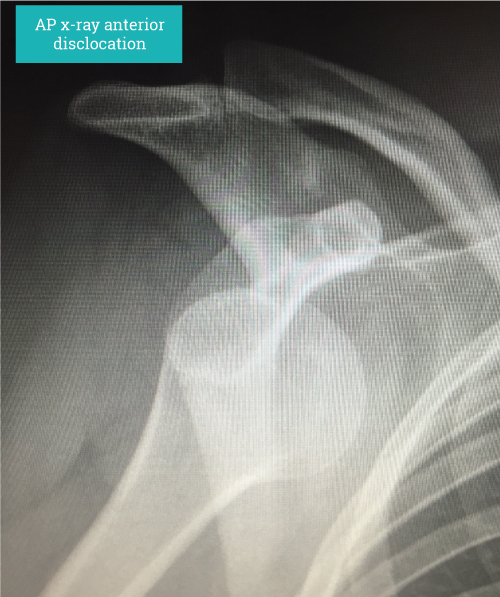

Diagnosis is based on clinical history and signs. Confirmation by an x-ray showing the dislocated shoulder can be helpful. Imaging such as MRI scanning will show the underlying structural problems such as a labral tear (soft tissue Bankart lesion), bony injuries such as glenoid rim fractures (bony Bankart lesion) and impaction fractures on the back of the humeral head (HillSachs lesion) where It has contacted the anterior glenoid during the dislocation. In older persons the risk of damaging the rotator cuff at the time of dislocation is increased and should be actively looked for as rotator cuff tears in these circumstances can be quite substantial.

“Diagnosis is based on clinical history and signs. Confirmation by an x-ray showing the dislocated shoulder can be helpful.”